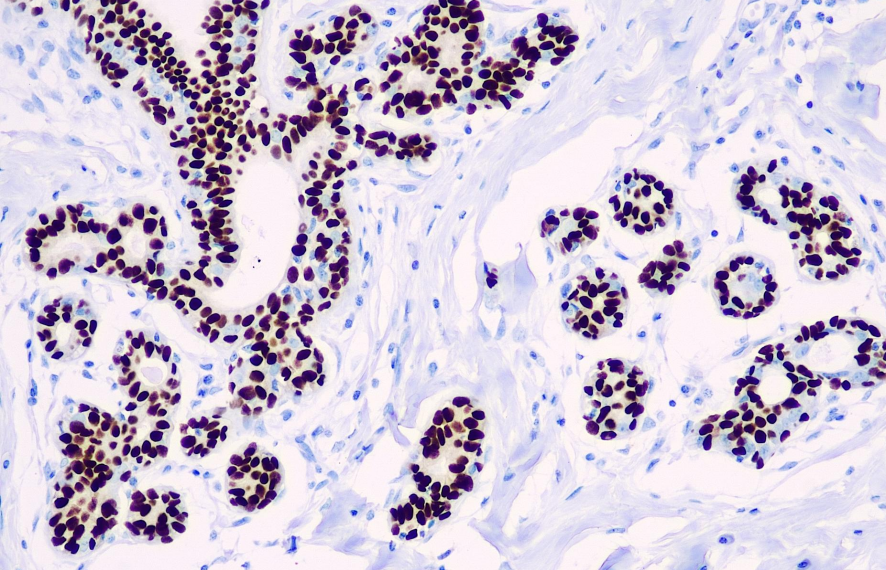

Cellular localization: nucleus

Positive control: melanoma/mammary gland

SOX-10, a member of the Sry-related HMG-box gene family, plays a role in the development of the neural crest and the differentiation and specialization of melanocytes, and functions as a nuclear transcription factor. It is highly expressed in residual fibrous proliferative melanomas and malignant peripheral nerve sheath tumors, but is not expressed or is lowly expressed in spindle-forming fibroblasts in skin scars, and can be used to distinguish residual fibrous proliferative melanomas from skin scars. SOX-10 is widely expressed in schwannomas and fibromas, but in other mesenchymal and epithelial tumors, it is only detected in myoepitheliomas and diffuse astrocytomas. In normal tissues, such as Schwann cells, bronchial secretory glands, and mammary myoepithelial cells, SOX-10 is also expressed. Therefore, the SOX-10 antibody is also used to distinguish various tumors of neural crest origin, mesenchymal tumors, epithelial tumors, and normal tissues.

The SOX-10 antibody reagent specifically binds to the SOX-10 molecular antigen. The immunohistochemistry kit containing the SOX-10 antibody reagent is suitable for the auxiliary diagnosis of tumors of neural crest origin, mesenchymal tumors, epithelial tumors, and others.